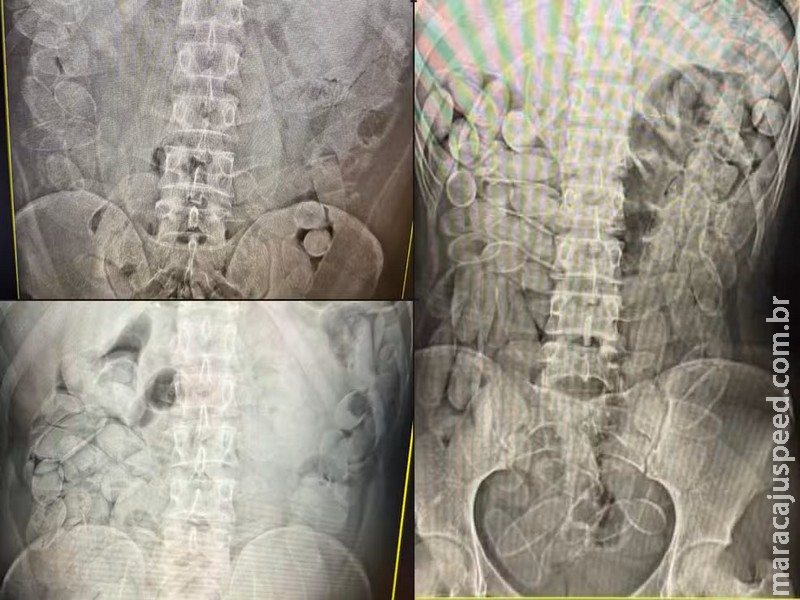

Cada pessoa engole, em média, cerca de 100 cápsulas de cocaína em tráfico internacional — Foto: Receita Federal

Quando há suspeita de transporte interno da droga, a pessoa é levada a uma unidade de saúde para exames de imagem. Se a presença das cápsulas for confirmada, o paciente passa a ser acompanhado por médicos até a eliminação ou retirada do material.

O método mais utilizado é a ingestão de cápsulas de cocaína. Cada pessoa ingere, em média, cerca de 100 cápsulas, o que totaliza aproximadamente 1,1 quilo de pasta base de cocaína por pessoa, conforme a auditora-fiscal da Receita Federal Tatiane Laranjo Amadeu Suhogusoff “Eles ficam de um a três dias com a droga no organismo, até eliminarem tudo naturalmente”, informou o órgão. A escolha por esse método tem um objetivo claro: dificultar a fiscalização, segundo Tatiane.

“A droga fica dentro do corpo e não aparece em scanners de bagagem comuns. Para identificar, é necessário uso de cães farejadores e exames de raio-X, o que exige estrutura e efetivo que nem sempre estão disponíveis”, explicou a Helberth, representante da ANTT.